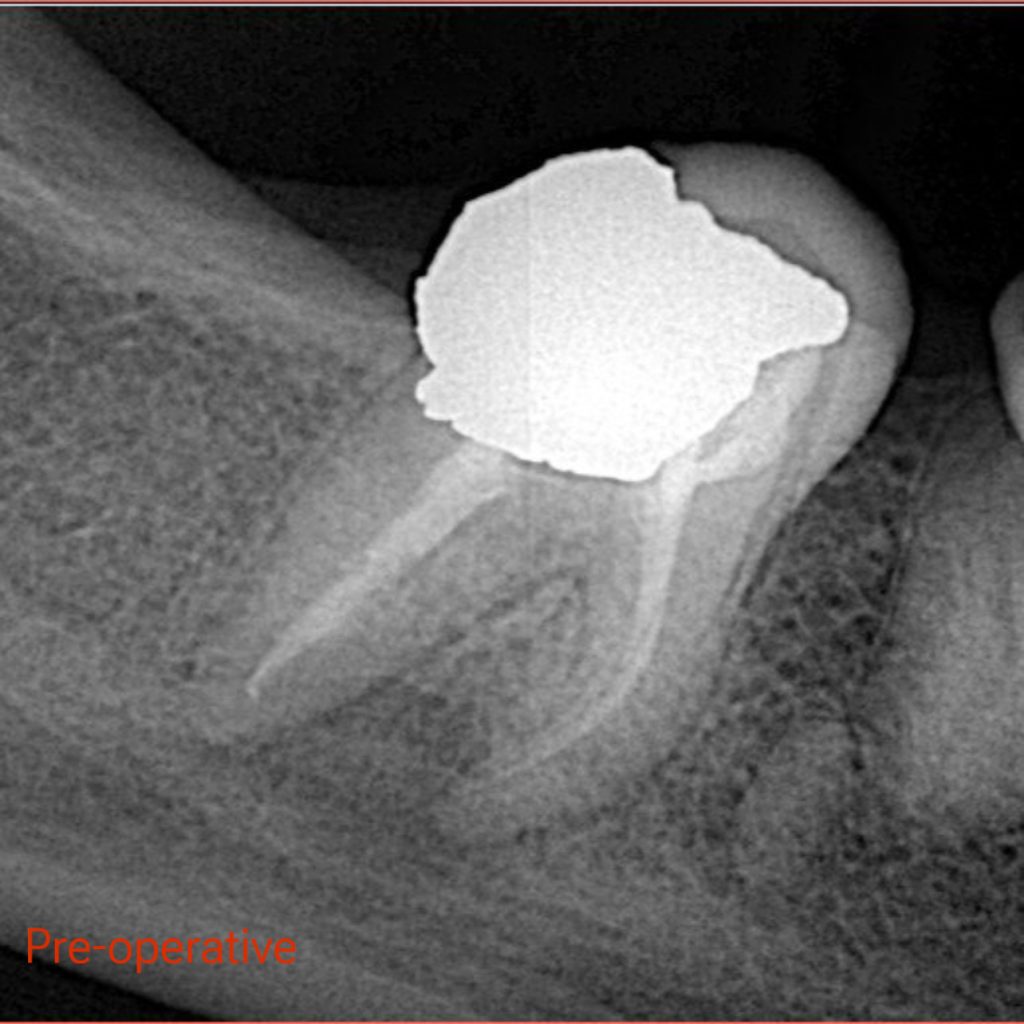

X ray showed many problems in previous Endodontic treatment with overhang amalgam filling

– Endodontic Re-treatment done, Obturation with Bioceramic Sealer and single cone